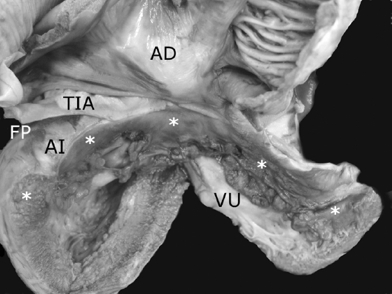

Los 2 corazones formaron parte de un situs solitus auricular, ambos con doble entrada a ventrículo único a través de una válvula auriculoventricular común cuyas valvas estuvieron adosadas a la pared ventricular; las grandes arterias normalmente relacionadas emergieron del ventrículo único con estenosis pulmonar infundibular y valvular (Fig. 5); el adosamiento y desplazamiento valvares cubrieron toda la porción de entrada y la zona trabecular posterior hasta la región apical con una gran auricularización del ventrículo único; estuvieron ausentes las cuerdas tendinosas y los músculos papilares (Fig. 6); la porción funcional efectiva del ventrículo se redujo a la zona trabecular anterior y a la región infundibular (Fig. 5). En el segundo corazón las grandes arterias estuvieron también normalmente relacionadas pero con dilatación y ambas emergieron del ventrículo único (Fig. 7). El adosamiento y desplazamiento valvares estuvieron reducidos a la porción proximal de la válvula por lo que la auricularización fue menor y mayor la porción funcional del ventrículo único (Fig. 8). Ambos corazones tuvieron un tabique interauricular pequeño con foramen primum (Tabla 1).

Figura 8 Vista interna posterior del corazón de la Figura 7 que muestra las aurículas en situs solitus conectadas con el ventrículo único a través de una válvula auriculoventricular común. Obsérvese el adosamiento valvar a la pared del ventrículo único en su porción proximal (asteriscos) y la presencia de nodulaciones fibromixoides en su porción distal libre. La porción adosada corresponde a la zona auricularizada y el resto a la porción funcional del ventrículo único. AD: aurícula derecha; AI: aurícula izquierda; FP: foramen primum; TIA: tabique interauricular; VU: ventrículo único..

Al comparar los corazones descritos en este trabajo con los que presentan anomalía de Ebstein de la válvula tricúspide con conexiones auriculoventriculares concordante y discordante se observan diferencias entre ellos. En la anomalía de Ebstein con conexión auriculoventricular concordante el adosamiento se presenta en forma de un espectro de grados de severidad con nodulaciones fibromixoides en las valvas liberadas, cuerdas tendinosas cortas y engrosadas y músculos papilares de estructura fibrosa o ausentes (Fig. 1). En la anomalía de Ebstein con discordancia auriculoventricular el adosamiento de la valva septal es de menor extensión y afecta solamente a esta valva (Fig. 9) y cuando esta malformación valvular se asocia a corazones con conexiones auriculoventriculares univentriculares, el adosamiento valvar puede ser extenso o solo en las porciones proximales (Figs. 6 y 8).